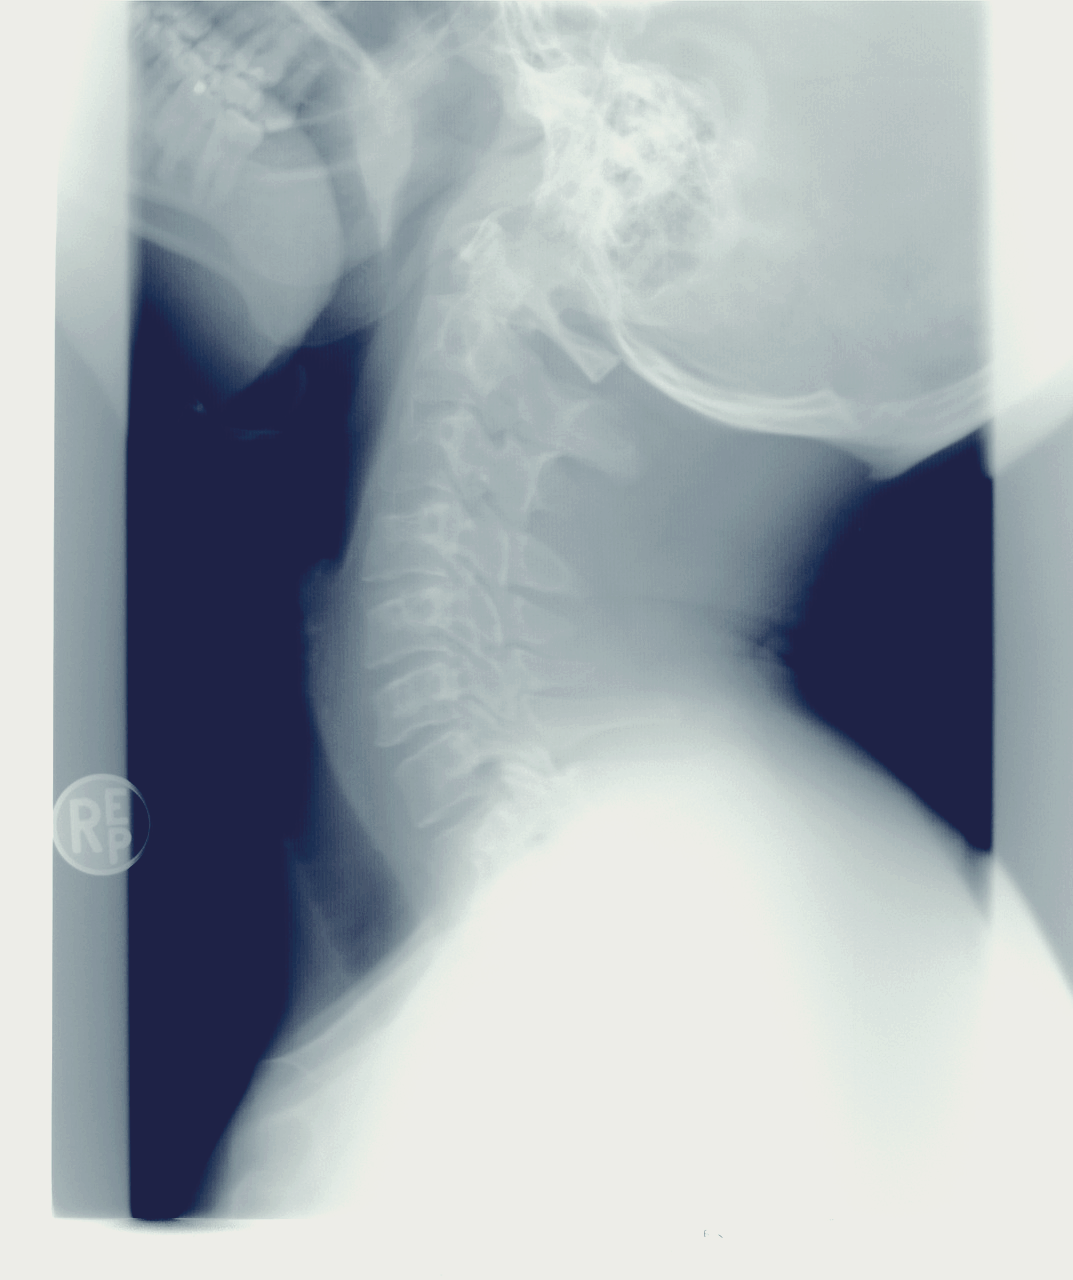

거북목이란?

거북목은 말 그대로 목이 앞으로 굽어져 있는 상태를 말합니다.

거북목이 발생하면 여러가지 불편한 증상이 발생할 수 있고, 심한 경우 일상생활을 하는 것에도 불편함이 이어질 수 있기 때문에 거북목은 교정하고 치료하는게 중요합니다.

거북목이 의심되는 경우 정확히 진단을 받고, 심한 정도를 확인하여 정확하게 거북목 교정을 받는 것이 중요하겠습니다.